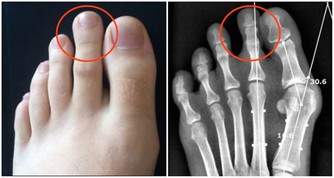

除此之外,起床後眼皮浮腫、腰酸乏力可能是腎病初期的表現,小便紅、小便時泡沫較多且持續時間長,四肢、臉上、身上的皮膚出現較多的紅點或紅斑,四肢關節酸痛等都應引起警覺。